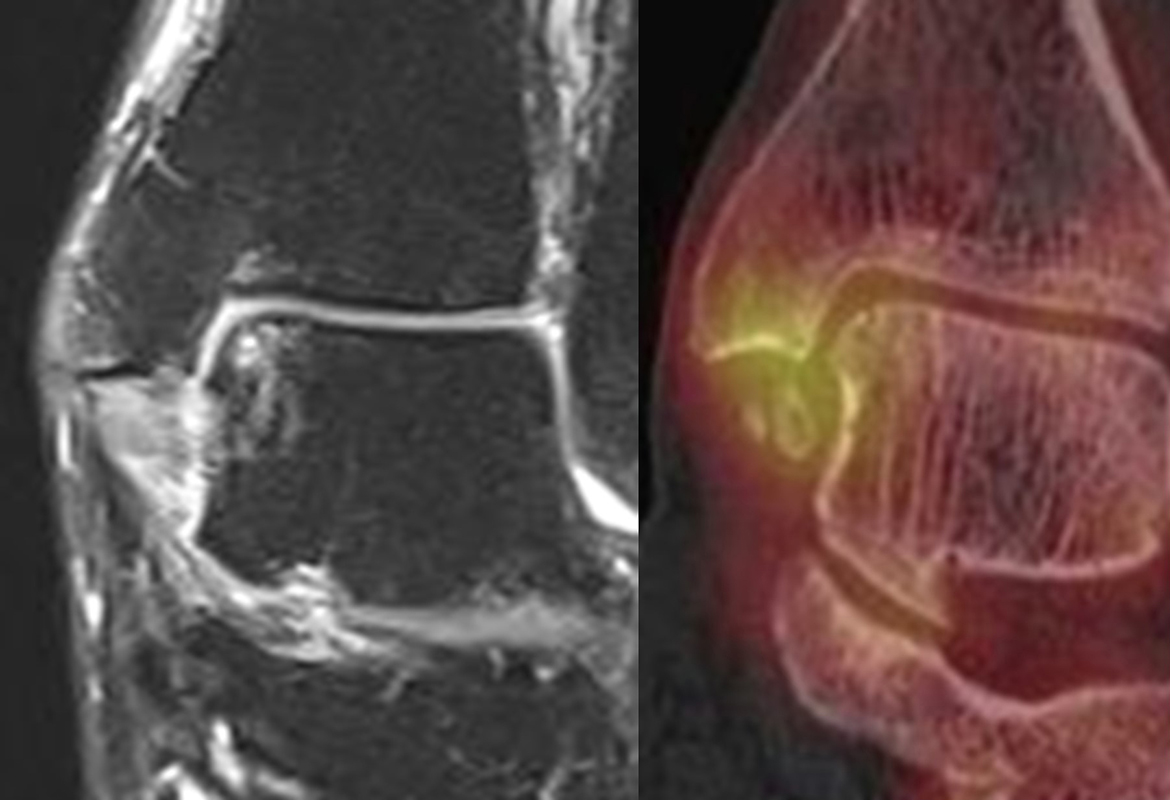

Abbildung 2.1.

Bildbeispiele symptomatische OCL

Zum Lesen der Bildbeschreibung und zur Vollansicht bitte das Bild anklicken. Bild: H. C. Rischke

Abbildung 2.2.

Bilder eines Patienten mit Z. n. mehrfachen Sprunggelenksdistorsionen in der Vergangenheit, besonders heftige Distorsion des linken Sprunggelenkes 5 Wochen vor der Untersuchung. Die SPECT/CT zeigt eine instabile osteochondrale Läsion mit deutlicher Aktivierung.